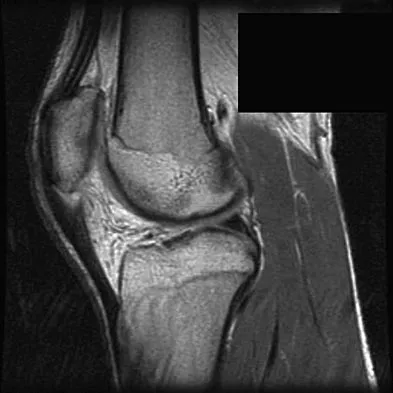

A 29-year-old woman who underwent an anterior cruciate ligament (ACL) reconstruction 6 months ago now reports difficulty achieving full knee extension, and physical therapy fails to provide relief. The knee is stable on ligament testing. Figure 3 shows the findings at a repeat arthroscopy. Treatment should now include

Explanation